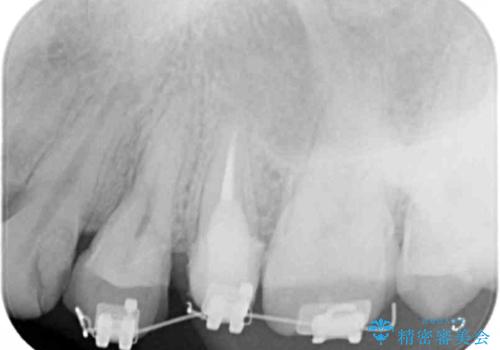

X線撮影を行い、隣接面に多発した虫歯と歯ぐきよりも深くなってしまった虫歯を小矯正をおこなったのちのセラミック治療で問題を解決します。

小矯正を行い深い虫歯を改善した後は、小手術を行うことで歯ぐき・周囲歯槽骨の状態を整えることでより安定した歯周環境を得ることができます。